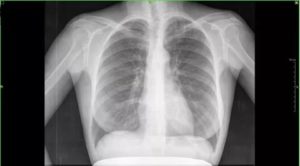

Рентгенограмма легких при пневмонии является классическим проявлением патологии. Приводим пример снимка при воспалительных изменениях легочной ткани (пневмония), чтобы читатели понимали, чем отличается норма от патологии.

Предлагаем ознакомиться с нижеприведенными снимками при пневмонии и в норме. Ответьте на вопрос, где рентгенограмма нормальная, а какая патологическая. Определите, на какой рентгенограмме пневмония.

Цифровой рентген органов грудной клетки №1 Цифровой рентген №2

Подскажем, что затемнение небольшое и локализовано над диафрагмой.

На представленной рентгенограмме лёгких визуализируется инфильтративная тень в наддиафрагмальной зоне слева. Корни тяжисты. Реберно-диафрагмальные синусы не завуалированы. Сердечная тень классической конфигурации. Патологии в мягких тканях не прослеживается.

Заключение: Рентген признаки левосторонней сегментарной пневмонии. Рекомендована рентгенография органов грудной клетки в левой боковой проекции для установки локализации затемнения.